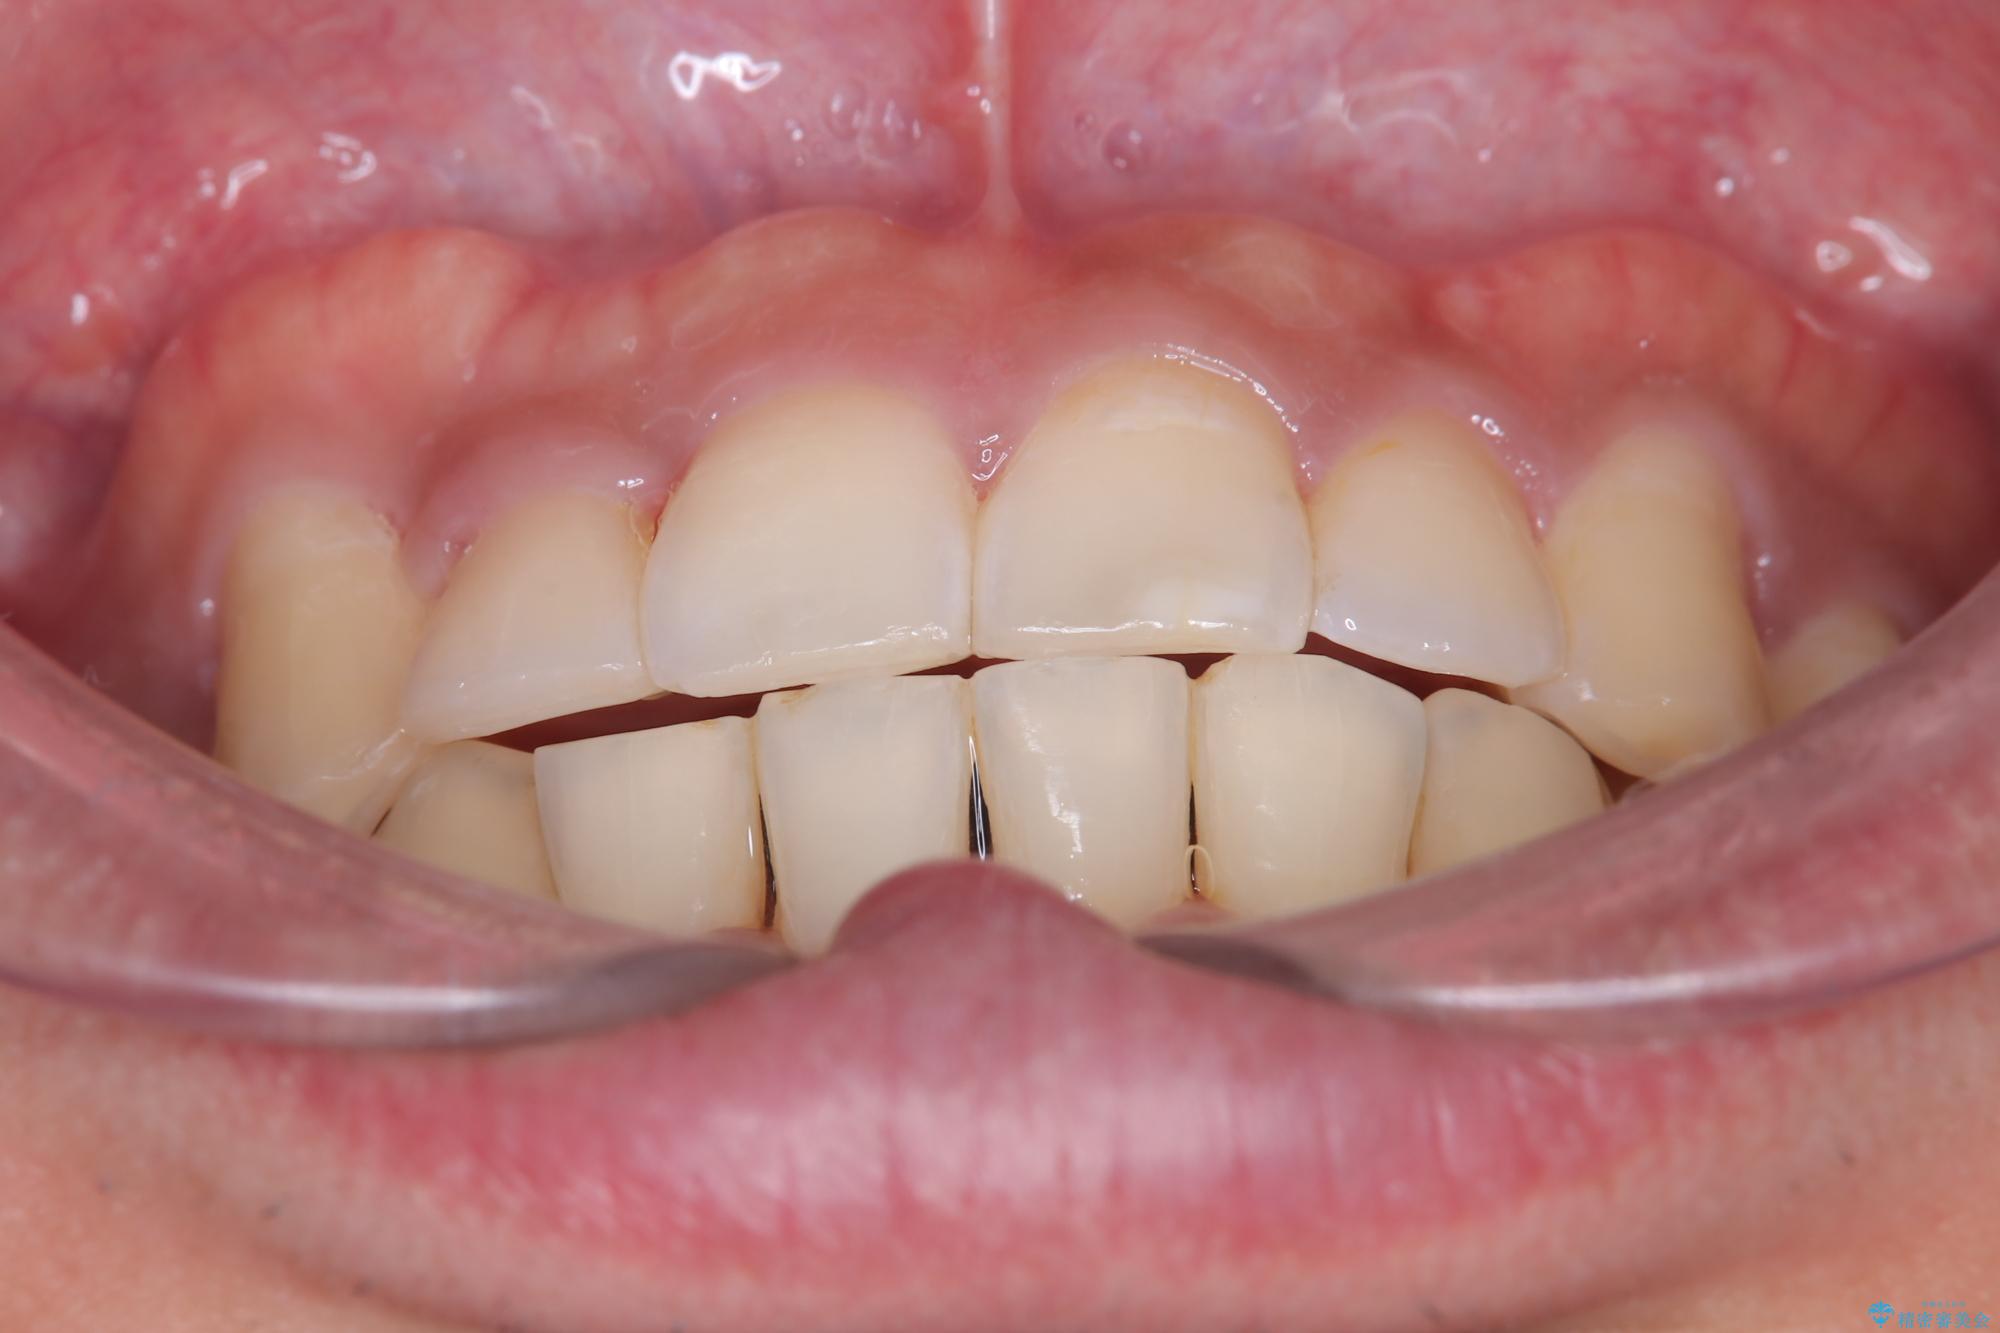

- 主訴:右上の八重歯と、下の歯の凸凹を治したい

右側2級、左側1関係だったため、右側上下第一小臼歯を抜歯し、ワイヤー矯正を行いました。

期間:2年6カ月